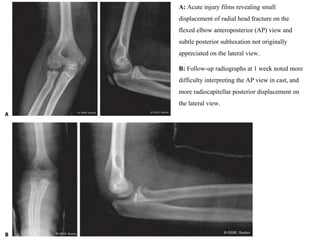

A: Acute injury films revealing small

displacement of radial head fracture on the

flexed elbow anteroposterior (AP) view and

subtle posterior subluxation not originally

appreciated on the lateral view.

B: Follow-up radiographs at 1 week noted more

difficulty interpreting the AP view in cast, and

more radiocapitellar posterior displacement on

the lateral view.

An MRI scan (C) was ordered urgently

and revealed a marked effusion and intra-

articular displacement of radial head

fracture and posterior radiocapitellar

subluxation.

D: Open reduction internal fixation was

performed to anatomically align the radial

head fracture and reduce the joint.

A: Acute injuryfilms revealing small displacement of radial head fracture on the flexed elbow anteroposterior (AP) view and subtle posterior subluxation not originally appreciated on the lateral view. B: Follow-up radiographs at 1 week noted more difficulty interpreting the AP view in cast, and more radiocapitellar posterior displacement on the lateral view.

An MRI scan(C) was ordered urgently and revealed a marked effusion and intra- articular displacement of radial head fracture and posterior radiocapitellar subluxation. D: Open reduction internal fixation was performed to anatomically align the radial head fracture and reduce the joint.